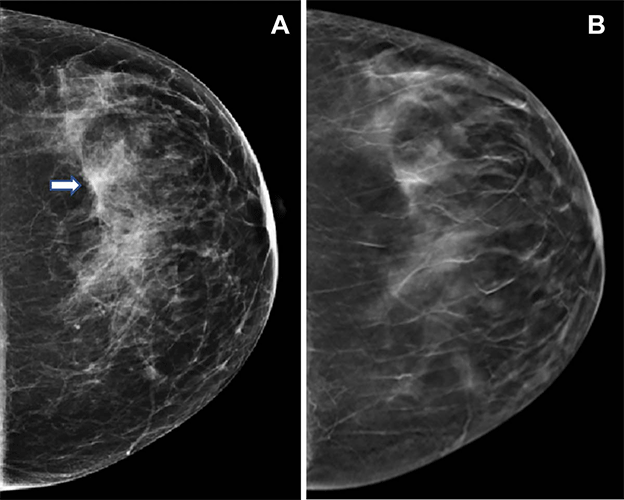

Images in a 47-year-old woman who presented for routine screening. (A) Craniocaudal digital mammogram shows scattered fibroglandular densities. On the left digital mammographic craniocaudal view laterally, an asymmetry (arrow) is present. (B) Left craniocaudal digital breast tomosynthesis image shows no suspicious lesion but rather a superimposition of normal fibroglandular and ligamentous structures. https://doi.org/10.1148/radiol.221571 © RSNA 2023